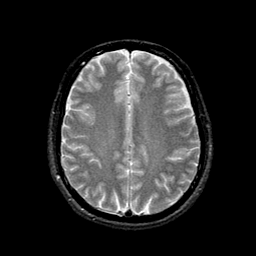

AIDS dementia: overlay -- Slice #12

[Home][Help][Clinical][Tour 1] Slice 12